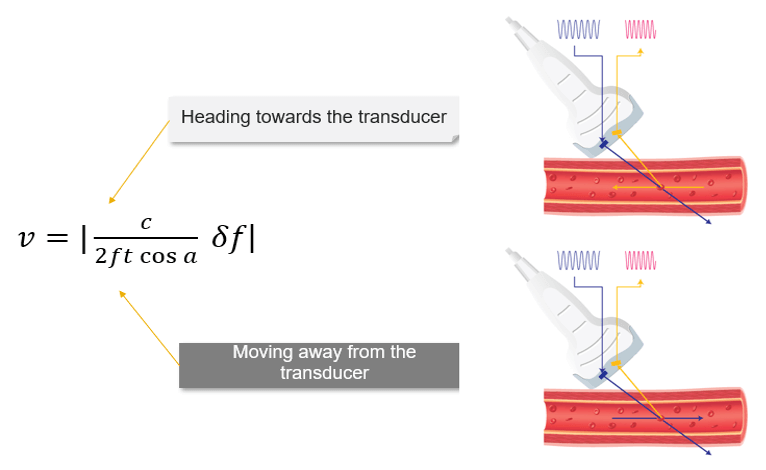

The Doppler equation shows the relationship between the transmitted Doppler shifted signal (Ft) and the blood flow velocity (V): V = c/(2ft cos a).δf, where the following represent: δf is the Doppler-shifted signal, Ft is the transmitted Doppler frequency, c is the propagation speed of ultrasound in soft tissue, V is the velocity of the moving blood, and a is the angle between the Doppler ultrasound beam and the direction of blood flow.

The number 2 is a constant indicating that the Doppler beam must travel to the moving target and then back to the transducer.